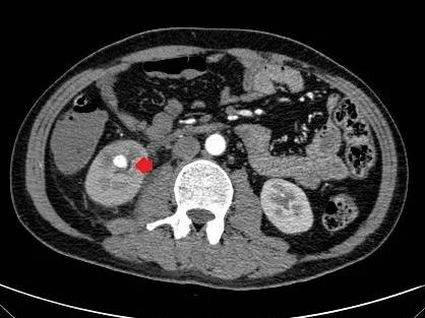

▲ 红色箭头为肾动脉分支动脉瘤

关键时刻,医院紧急组织多学科会诊,受邀参加的介入科会诊后考虑肾脏动脉瘤破裂出血可能性大,通过联系医学影像科完善肾动脉CTA检查。不出所料,一个直径约2cm的“炸弹”映入眼帘。介入科吕军主任医师检查后考虑存在活动性出血,若不采取积极措施干预,杨大哥随时可能出现失血性休克,让脑梗进一步加重,甚至危及生命。通过耐心地解释沟通,家属打消了顾虑,并决定同意手术。